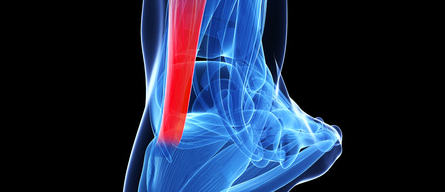

Le tendon d'Achille

Le tendon d'Achille relie le muscle du mollet à l'os du talon. Il est constitué d'une multitude de filaments qui jouent le rôle d'un élastique lors des mouvements de la cheville, de la jambe et est soumis à de fortes tractions.

Il existe différents types de lésions du tendon suivant les zones touchées.